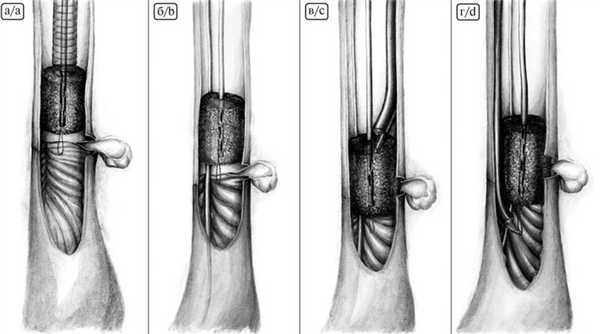

При создании эндоскопической ВАС использовали губчатую систему с открытыми сообщающимися ячейками для лечения осложненных и хронических раневых инфекций размером 10×7,5 см и толщиной 3,3 см (рис. 4, А). Рис. 4. Пошаговое моделирование вакуумно-аспирационной системы. А — губчатая система с открытыми сообщающимися ячейками размером 10×7,5 см и толщиной 3,3 см; Б — моделирование губки в форме цилиндра; В — назогастральный зонд, на котором моделировали систему; Г — фиксация губки на дистальном конце зонда; Д — фиксация губки проксимально; Е — окончательный вид системы. Такие размеры губки позволяли сделать 2 ВАС с использованием стандартного зонда для аспирации содержимого желудка.

Губку моделировали в форме цилиндра диаметром, не превышающим диаметр пищевода, и длиной, перекрывающей минимум на 2 см дистальную и проксимальную границы зоны несостоятельности (см. рис. 4, Б). В губку проводили «желудочный» зонд и фиксировали его 2 швами — на дистальном конце зонда и проксимально (см. рис. 4, В, Д). Здесь же из лигатур формировали 2 петли для позиционирования губки. На рис. 4. Е представлен окончательный вид ВАС.